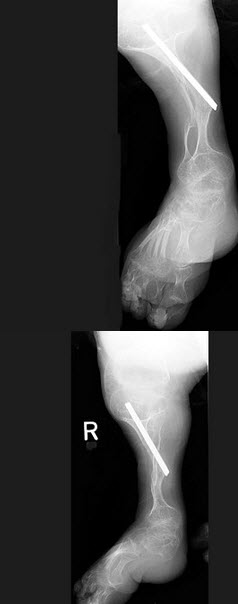

51、单项选择题

女,26岁,右踝部疼痛,结合图像,最可能的诊断是()